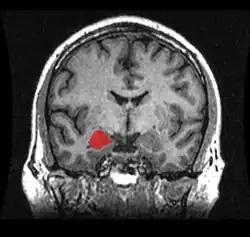

As bases neurais da agressão têm sido consistentemente estabelecidas nos últimos anos, onde regiões cerebrais e neurotransmissores, bem como as suas ligações com diversos genes, hormônios e transtornos psiquiátricos, têm sido triadas.[3][7] Dentre as estruturas corticais, o Córtex Pré-Frontal (CPF) é a região cerebral mais amplamente associada com a agressão impulsiva em humanos. O CPF desempenha um papel central no controle de comportamentos, no direcionamento a metas e na tomada de decisões. Pacientes com lesões no CPF ventromedial (CPFvm) tiveram uma maior probabilidade de mostrar confrontos verbais e agressividade, se comparados com pacientes com lesões em outras áreas cerebrais e com grupo-controle sem lesões.[19] Homens com transtorno de personalidade antissocial têm mostrado alterações no COF, no Córtex Cingulado Anterior (CCA), na Insula e na Amígdala. Similarmente, pacientes com Transtorno de Personalidade Borderline e Transtorno Explosivo Intermitente também apresentam características de funcionamento atípico nessas regiões. Estudos de neuroimagem têm confirmado uma disfunção e redução no volume do COF, CCA e CPFvm em pessoas com comportamento agressivo.[20][3]

Um número crescente de evidências tem corroborado a função da amígdala como uma das regiões cerebrais mais importantes para agressão na espécie humana. A amígdala, envolvida no processamento de estímulos biologicamente relevantes e reações emocionais, e o CPF, são reciprocamente conectados.[7][3][20] Além disso, neurotransmissores como serotonina, GABA e dopamina, e hormônios como testosterona, progesterona, cortisol e vasopressina, apresentam um relevante papel determinante para a manifestação do comportamento agressivo.[3]